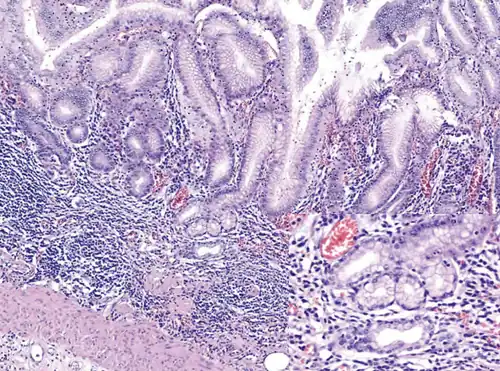

Histopathology of antral mucosa with atrophy. H&E 10x. Antral gastric mucosa with accentuated atrophy because of replacement by extensive intestinal metaplasia. -

Histopathology of fundic mucosa with atrophy. H&E 10x; square 20x. Fundic-corporal gastric mucosa with extensive loss of gastric glands, partially replaced by pseudo-pyloric metaplasia.